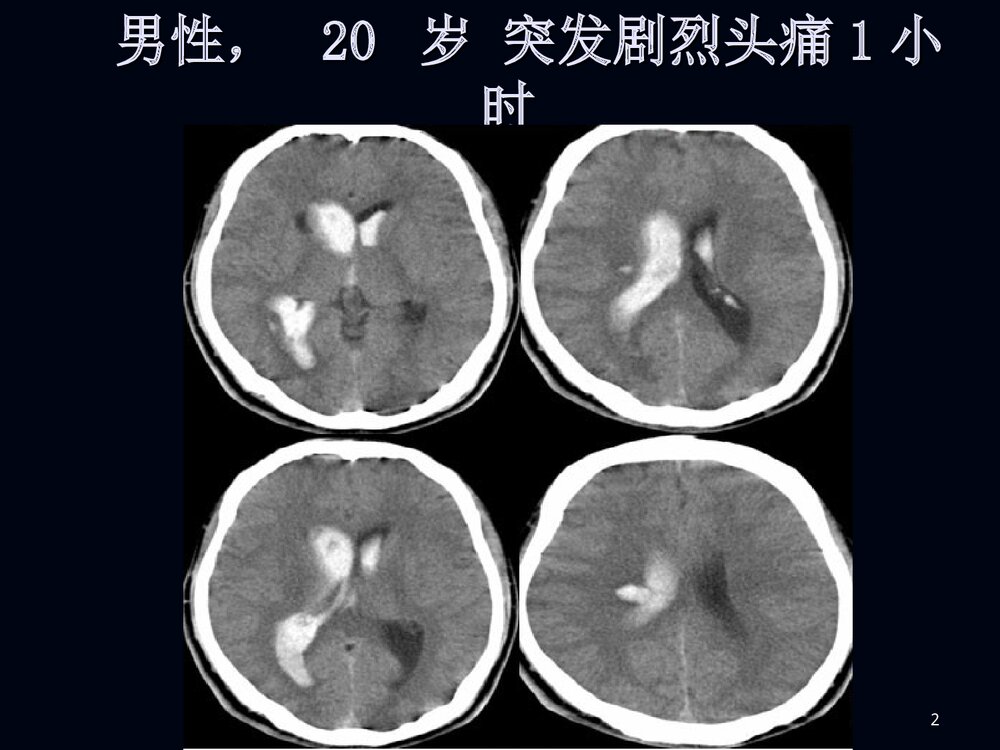

1烟雾病临床和影像诊断烟雾病临床和影像诊断2男性,男性,2020岁突发剧烈头痛岁突发剧烈头痛11小小时时3脑室穿刺脑室穿刺引流后增引流后增强强CTCT4MRIMRI5MRAMRA67病例病例22F、38Y,右侧肢体无力伴言语不清24天8MRIMRI910病例1DSA11烟雾病烟雾病病例2脑底异常血管网1213烟雾病烟雾病概述概述病理病理分型、分期分型、分期临床表现临床表现影像表现影像表现诊断诊断鉴别诊断鉴别诊断治疗治疗14概述概述烟雾病是以颈内动脉虹吸部或大脑前、中烟雾病是以颈内动脉虹吸部或大脑前、中动脉起始部缓慢的进行性的自发性狭窄或闭塞、动脉起始部缓慢的进行性的自发性狭窄或闭塞、并在脑底出现异常的小血管网为特点的一种脑血并在脑底出现异常的小血管网为特点的一种脑血管病。管病。在脑血管造影时,脑底...